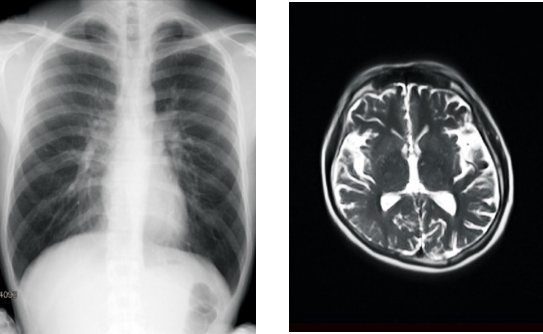

賛育会病院では2021年10月11日より、「カルテコ」で健診情報が閲覧可能になりました。今回新たに、健診・人間ドックで撮影したレントゲン・マンモグラフィ・CT(コンピュータ断層撮影)・MRI(磁気共鳴画像診断)などの検査画像が閲覧できるようになります。21年1月以降の過去のデータまでさかのぼって閲覧することができます。

「カルテコ」で閲覧できるようになる検査画像のイメージ